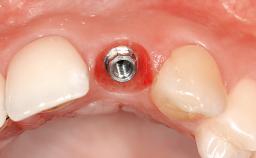

Immediate Implant - Immediate Temporary: Guided Surgery in the Esthetic Zone

In this video Dr. Nikos Mattheos demonstrates the full diagnostic, planning and treatment sequence of an immediate implant with an immediate prefabricated provisional restoration in the esthetic zone. A 28 years old female patient presents with discoloration and increasing mobility of tooth 11. Advanced stage of external resorption is diagnosed. Patient's high esthetic demands combined with intact gingival architecture and periodontal health makes her a good candidate for immediate placement and restoration to preserve the gingival contour. Surgical and restorative treatment is planned with digital workflow based on data from CBCT and intraoral scan. An immediate temporary crown is manufactured for placement at the day of the surgery. Flapless extraction is performed, and the implant placed with guided surgery. Consequently, the buccal gap of the socket is augmented with Xenograft, while the soft tissue space maintained with a collagen plug. Finally, a provisional crown is immediately placed on the implant with a titanium temporary abutment and an emax prefabricated crown.